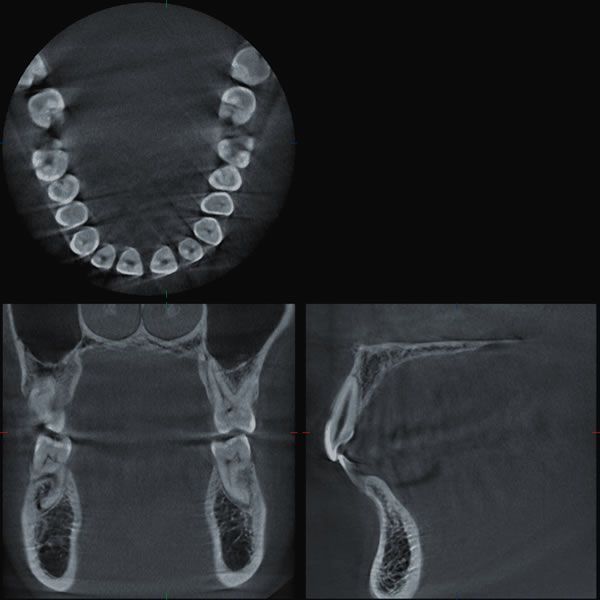

Hochmoderne Röntgentechnologie

Mit dem Veraviewepocs 3D R100

verfügen wir über hochmoderne Röntgentechnologie des renommierten Herstellers Morita. Es handelt sich um ein Kombinationsgerät, das sowohl Übersichtsaufnahmen des Gebisses („Panoramaaufnahmen“), Fernröntgenseitenbilder (zur Kopfvermessung) und sogar 3D-Aufnahmen erstellt.

3D-Planung von Implantaten: Unter anderem ist mit diesem Röntgengerät eine dreidimensionale Planung von Implantaten

möglich: Basierend auf den 3D-Bilddaten wird die Position der Implantate schon im Voraus auf den Zehntelmillimeter genau am Monitor festgelegt. Gerade in schwierigeren Ausgangssituationen, beispielsweise bei zurückgegangenem Kieferknochen, sind damit sicherere und schonendere Behandlungen und meist ästhetischere Ergebnisse möglich.

Wurzelkanalbehandlung

(Endodontologie): Auch bei Wurzelkanalbehandlungen können 3D-Aufnahmen wertvoll sein. Sie ermöglichen eine verbesserte Diagnose und Beurteilung bei schwer zu erkennenden Wurzelrissen, Veränderungen an der Wurzelspitze oder Wurzelabbau (Resorption). 3D-Aufnahmen können helfen, solche Zähne zu erhalten.

Der Veraviewepocs 3D R100

kommt darüber hinaus mit geringerer Strahlendosis bei hoher Bildqualität aus. Dies alles sind Vorteile, die uns und Ihnen gleichermaßen zugutekommen.